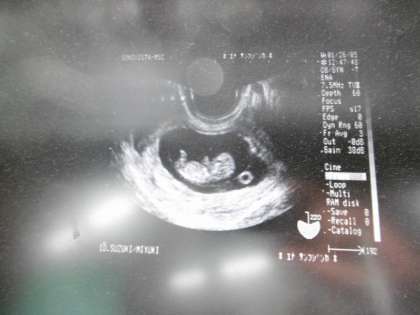

今月のふれあい学習として,二年生は出産時の赤ちゃんについてのお話をもとに「命の大切さ」について学びました。

おなかの中の赤ちゃんの大きさなどを知った子どもたちは,「えー!!」と驚きながらも真剣に授業を受けることができていました。